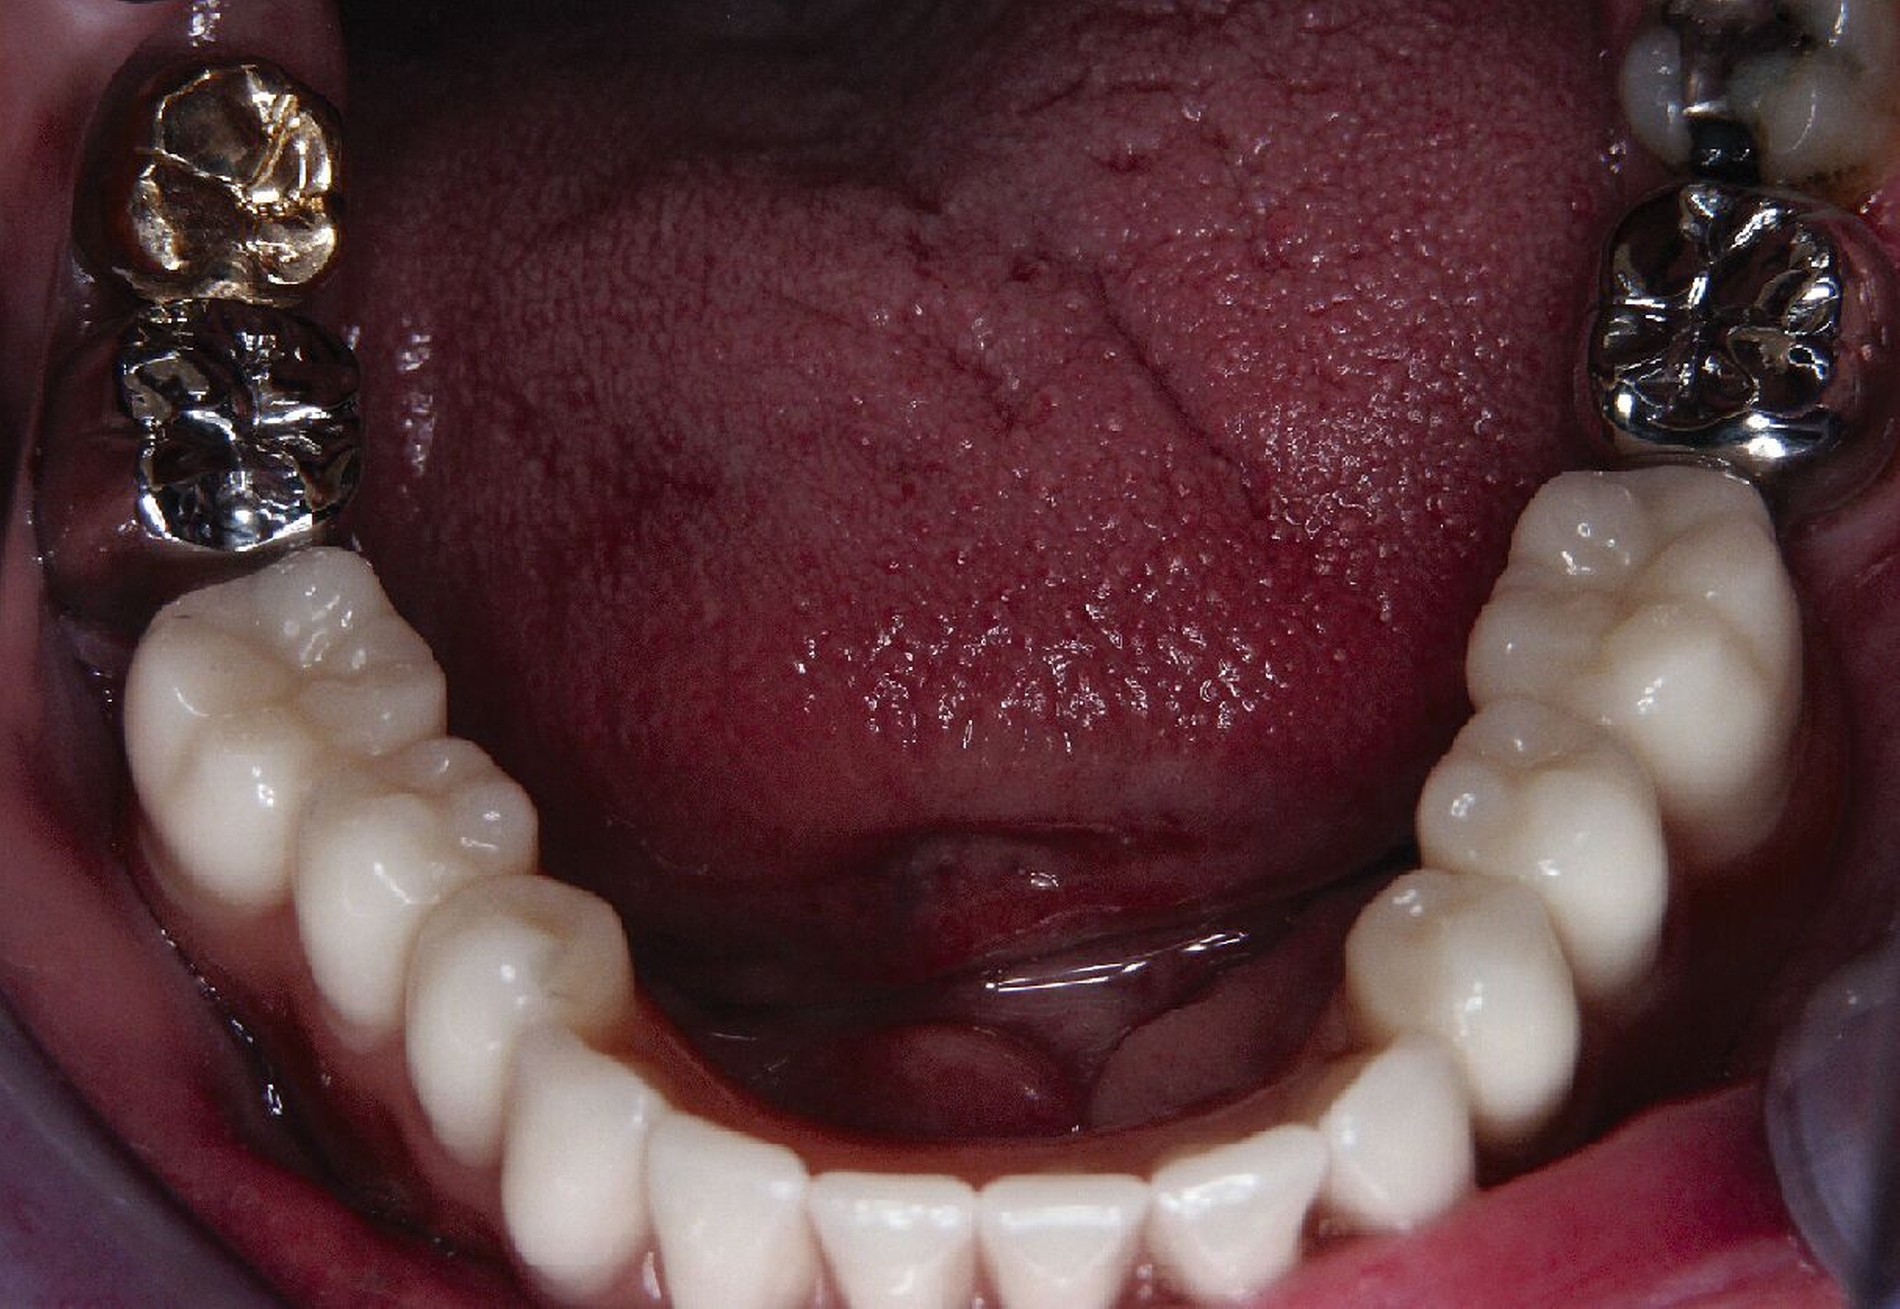

Nachdem der Patient bei einem Berufsunfall mit Ausnahme der zweiten Molaren und der Weisheitszähne alle Zähne im Unterkiefer verloren hatte, erfolgte 1996 im Alter von 44 Jahren die definitive Lückenversorgung. Hierzu wurden eine verschraubte Brückenkonstruktion (044-034-043-044) sowie zwei verblockte Kronenpaare auf insgesamt acht Implantaten eingesetzt. Nach sieben Jahren Tragedauer wurde an mehreren Implantaten röntgenologisch ein Knochenabbau festgestellt. Verkürzte Kontrollintervalle mit professionellen Zahnreinigungen und intensiven Instruktionen zur Interdentalhygiene konnten nicht verhindern, dass nach weiteren sieben Jahren Anfang 2011 der Knochenverlust an den meisten Implantaten auf 50 bis 80 Prozent zunahm (Abb. 1a).

Eine präoperativ vorbereitete Interimsprothese, die über zwei gegossene Bonwill-Klammern sowie das verbliebene Implantat in regio 35 stabil abgestützt war, diente gleichzeitig als Verbandsplatte (Abb. 1f). Auf eine Glättung scharfer Knochenkanten oder die Nivellierung der Kieferkämme wurde verzichtet, um einen iatrogenen Knochenverlust zu vermeiden und das regenerative Potenzial des verbliebenen Knochens zu nutzen (Abb. 1g). Bereits bei der röntgenologischen Kontrolle nach drei Monaten war eine deutliche Zunahme des Knochens im Bereich der alten Implantatpositionen zu erkennen (Abb. 1h). Eine Nachimplantation von vier Implantaten in den Positionen 32, 34, 42 und 44 erfolgte neun Monate nach der Explantation und einer vorangegangenen Verbesserung der Weichgewebsbedeckung durch multiple freie Schleimhautransplantate vom harten Gaumen. Die knöcherne Regeneration unter der gut abgestützten Modellgussprothese verlief so günstig, dass sich der vertikale Höhenverlust des Alveolarkamms im Bereich der gescheiterten Implantate auf circa 2 mm begrenzen ließ. Das zur Entlastung der Kieferkämme und der einheilenden Implantate außerordentlich hilfreiche Implantat in regio 35 wurde erst nach dem Einheilen der nachgesetzten Implantate entfernt. Nach der Einheilzeit der Implantate von weiteren drei Monaten wurde eine kombiniert Zahn/Implantat-gestützte Teleskopprothese mit intraoral verklebten Galvano-Sekundärkronen eingegliedert (Abb. 1k bis 1m). Inzwischen ist diese, wie eine herausnehmbare Brücke abgestützte UK-Prothese seit zehn Jahren funktionstüchtig ohne Zeichen einer Periimplantitis an den vier Implantaten.